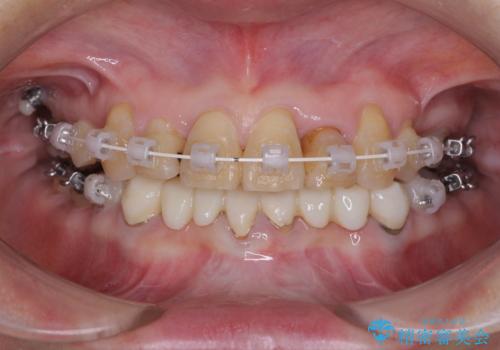

- 常に外れている下顎のブリッジと、前歯のデコボコと色を気にして来院された患者様です。

前歯のデコボコおよび奥歯の咬み合わせを改善するために、上顎左右の小臼歯を欠損スペースを利用して歯列を整え、矯正治療後に気になる上下前歯などをオールセラミッククラウンで美しく仕上げていくこととしました。